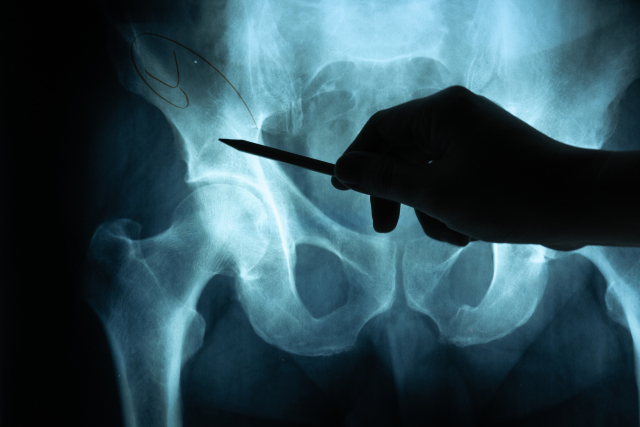

24일(현지시간) 지무신문 등 현지 매체에 따르면 최근 중국의 한 소아과 의사가 생후 8개월 영아의 건강검진을 진행하던 중 엉덩이 주름이 비대칭인 것을 발견했다.

엉덩이 주름 비대칭은 고관절 이형성증이나 근육 신경계의 이상을 의심해 볼 수 있는 질환이다. 이에 의사는 곧장 아이에 대한 추가 검사를 실시했다. 그 결과 음낭에서 나사못처럼 보이는 물체가 확인됐다.

의사는 외과와 영상의학과에 도움을 요청했고, 의사들은 아이가 나사못을 삼켰을 가능성을 언급하며 상급병원에서 수술을 진행할 것을 권유했다.

아이는 즉시 대형병원으로 이송됐고, 복강경 수술을 통해 음낭에 있던 나사못을 무사히 제거했다.